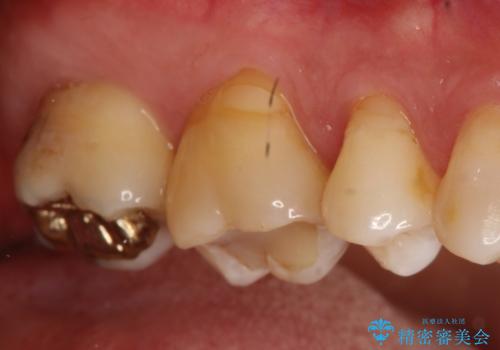

- 以前治療したところが欠けてしまったところを見てほしいとのことで来院されました。

右上の後ろから2番目の歯に詰めてあったものが、一部欠けてしまっていました。

そして隣接部にも虫歯が確認されました。

ゴールドインレーにて治療することとなりました。